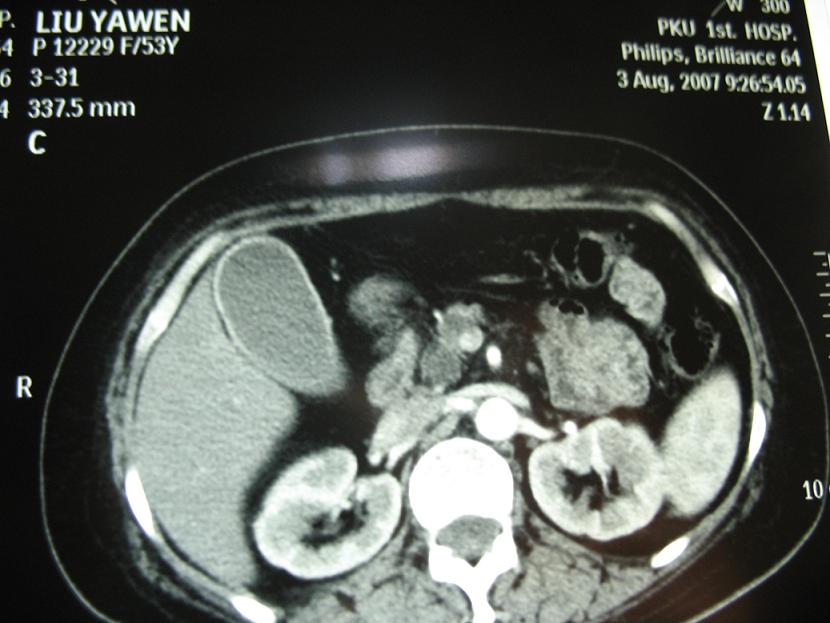

标题: CT17151:女 53岁 腹痛数月余 轻微黄疸 [打印本页]

女 53岁 腹痛数月余 轻微黄疸

1)考虑胰头癌。2)胆囊炎。

壶腹周围占位(钩突ca?)

胰腺钩突mt

支持胰腺钩突ca伴胆系梗阻,胆囊炎

考虑 胰头癌可能性大。